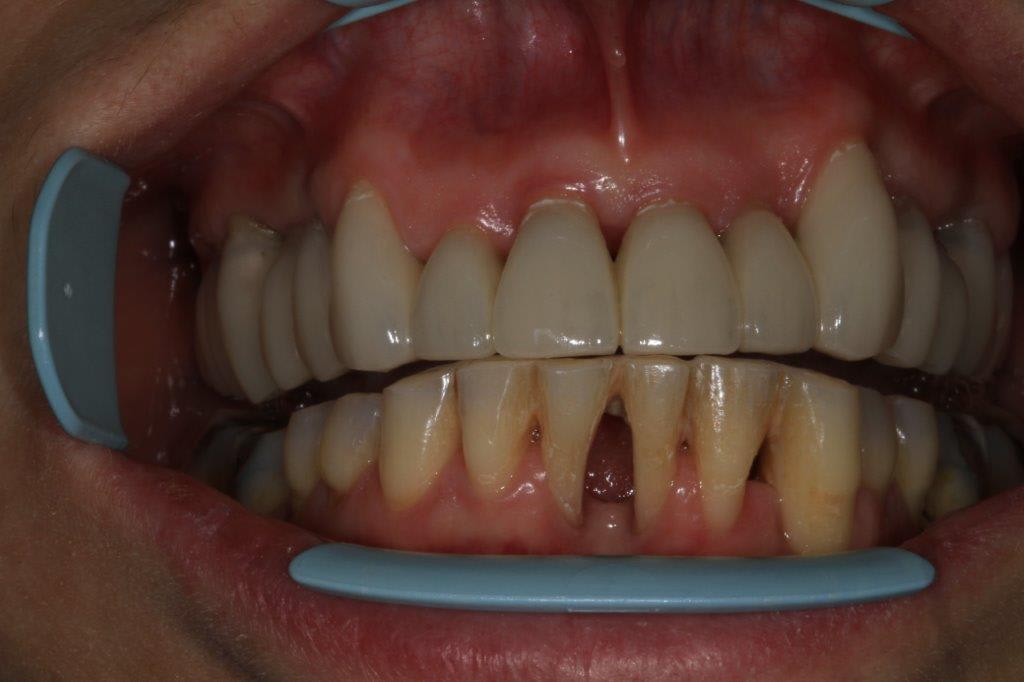

Contrôle à une semaine...

La gencive de 11 et 12 n est pas jolie .

Et ce n est pas un pb induit par la prothèse, pcq c était déjà présent sur les photos initiales .

Tu vois c est pour ça que je ne crois pas à la chimie .

T as beau la chimistrer tant que tu veux la gencive , si tu ne la fraises pas , pipée elle est , pipée elle restera.

Pas la prothèse, mais j'ai été un peu agressif à la fraise de polissage sur l'attache et effectivement ça n'est encore pas revenu, d'autant plus qu'avant les photos j'ai un peu gratouillè ala curette, les restes éventuel de ciment

Wait and see

Non non c est pas ca

C était pareil au début

A mon avis c est pcq qu il n y a pas assez d os en proximal pour soutenir la gencive

c'est clair qu'il n'y a plus beaucoup d'os, mais j'ose croire que ça va aller...